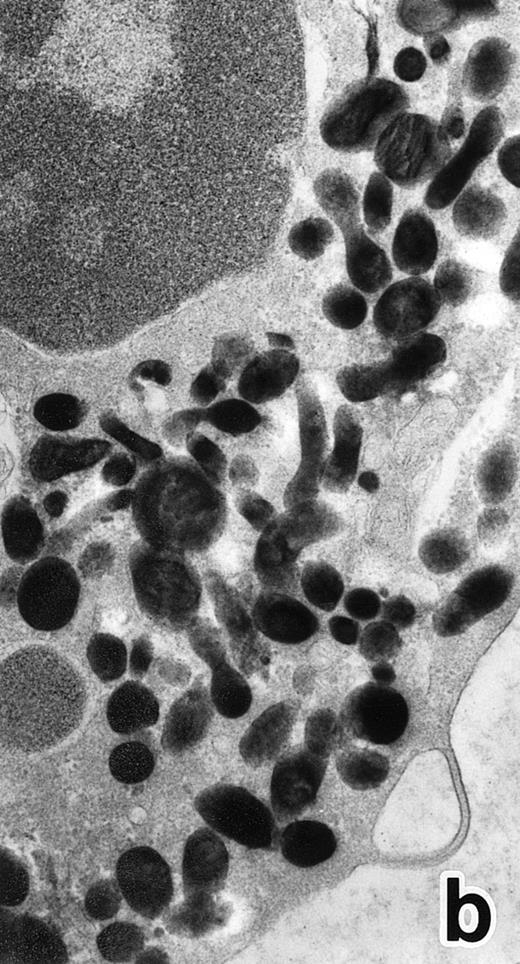

APL cells in culture.APL cells in patient no. 3 were cultured in the presence of ATRA or G-CSF for 7 days, and their morphological changes were examined under a light microscope. After 5 days of culture with ATRA the cells displayed a tendency toward maturation, including nuclear lobulation, chromatin condensation, and a decrease or disappearance of azurophil granules, similar to that observed in bone marrow cells. The cells cultured with G-CSF for 7 days, on the other hand, retained a promyelocytic appearance with numerous azurophil granules that even seemed to have increased in size and/or number (data not shown). Electron microscopic examination showed the nuclei of the cells cultured with ATRA to be irregularly lobulated with marginally condensed heterochromatin and the lobulated nuclei to be often connected by nuclear filamentous structures, in a manner similar to the cells seen in the bone marrow (Fig 8). These cells contained numerous MPO-positive primary granules, including irregularly shaped granules, but no MPO-negative specific granules were identified.

(a) A PMN that emerged in the APL cell culture of patient no. 3 in the presence of ATRA for 1 week. From the lobulated nuclear configurations and condensed heterochromatin, this cell looks like a PMN. However, the cytoplasm contains many MPO-positive primary granules but no secondary granules. (MPO-stained section, original magnification × 14,900.) (b) Higher magnification of a portion of the cell in (a), showing that the cytoplasmic granules are all MPO-positive. (MPO-stained section, original magnification × 30,100.)